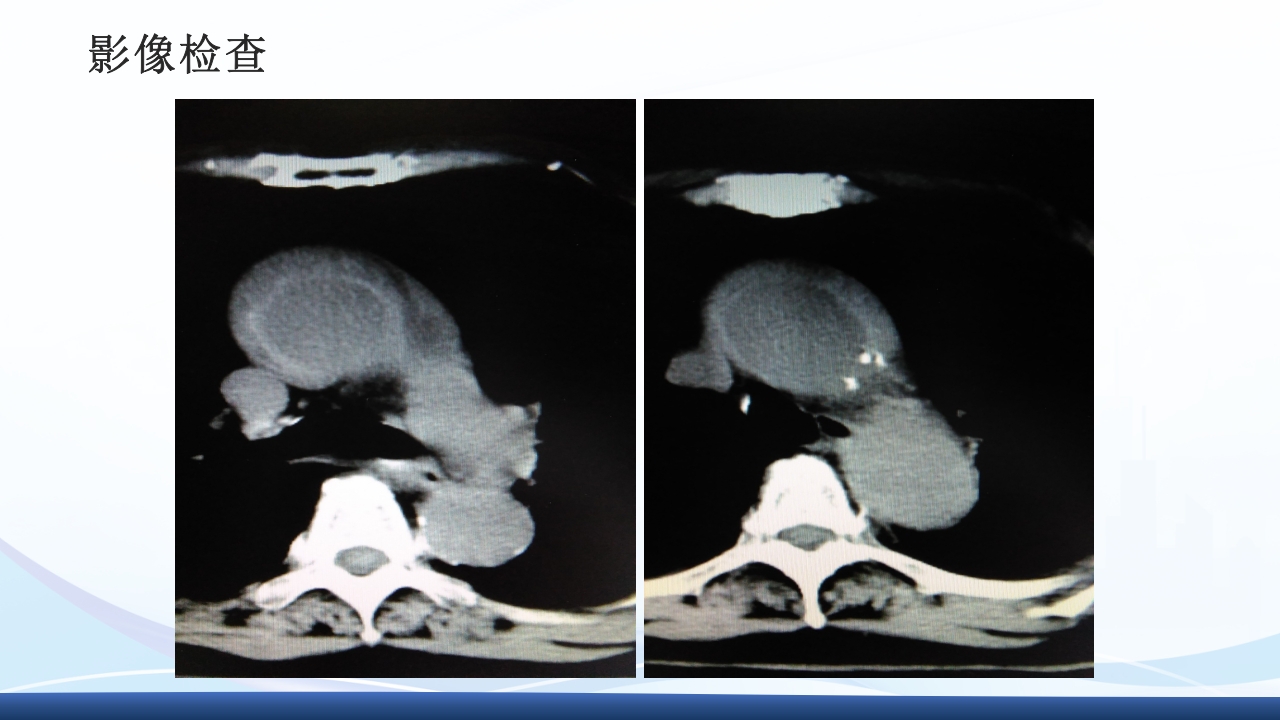

大纲 1 主动脉夹层的概念 2 病因与发病机制、分型 3 临床表现3 、辅助检查 4 主动脉夹层的诊断、治疗 5 病例介绍 64 护理诊断与措施、健康宣教 解剖图 解剖图 主动脉夹层的概述 主动脉夹层(aortic dissection AD)指主动脉壁中层 撕裂、分离,使主动脉壁内形成血肿,并沿纵向延伸。 AD最常发生在50-70岁的男性,男女性别比约2-5:1, 是与人类主动脉有关的最常见的死亡原因。 Thoraci caorta Abdomin alaorta Aortic dissection Aorta Blood in wall of artery Blood in artery 病因 结缔组织遗传缺陷性疾病:如马方(Marfan)综合征、埃-当(Ehlers-Danlos)综 合征、先天性主动脉缩窄、二叶主动脉瓣及二尖瓣脱垂等患者。 高血压:临床与动物实验发现,不是血压的高度...